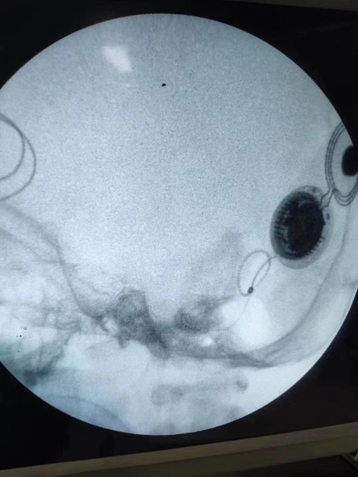

术中监测悉数电极阻抗值正常,各通道神经反应遥测波形优秀。

术后拍片表现人工耳蜗植入位置正常。